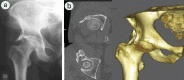

Introduction: The pelvic digit or pelvic rib is an unusual congenital anomaly with a finger or rib like bone formation in soft tissues around normal pelvic skeleton. This is a benign lesion and mostly an Incidental finding on radiographs. Most reported cases are asymptomatic and do not require intervention. We report a case of symptomatic pelvic rib that required surgical excision.

Case report: A 57-year-old man presented with a long history of pain and functional limitation in his right hip. On plain radiographs a fusiform bony structure adjacent to the acetabulum was noted. The imaging tests (MRI and CT) suggested the diagnosis of pelvic digit. We performed surgical excision of the lesion through anterior Smith-Peterson approach. The histopathology showed presence of corticomedullary structure. After surgery the patient's symptoms were relieved.

Conclusions: It is important to recognize this lesion on plain radiographs and to confirm by CT scan and make differential diagnosis. In the majority of cases the pelvic digit is asymptomatic and no treatments is needed. However in cases where symptoms can be attributed to pelvic digit an excision will relieve the pain and disability.